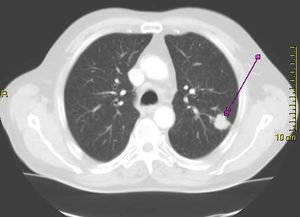

مسح مقطعي يظهر ورم سرطاني في الرئة اليسرى